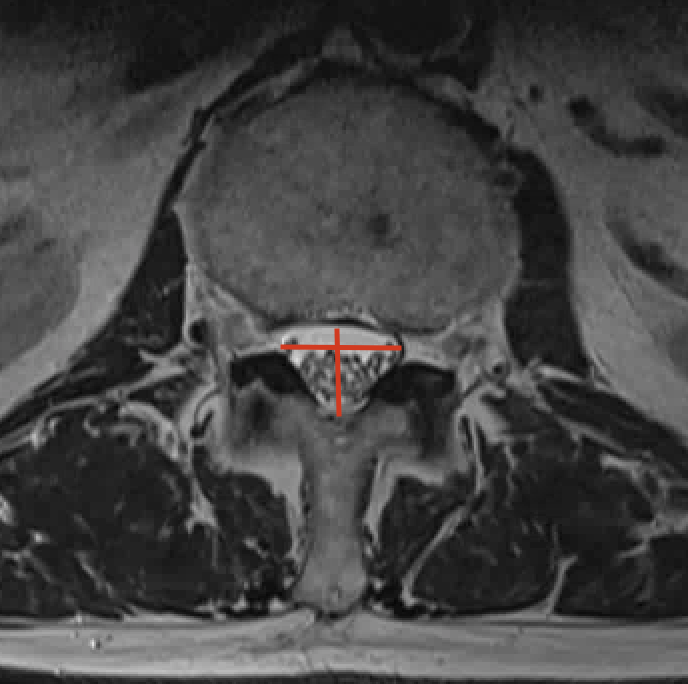

De diagnose wordt het best gesteld door middel van een NMR (=MRI) van de lumbale wervelkolom. Wanneer deze niet mogelijk is door claustrofobie of de aanwezigheid van pacemaker of neurostimulator, is een CT scan van de lage rug een goed alternatief. Bijkomend kan een EMG van de onderste ledematen het zenuwlijden bevestigen. Dit zenuwonderzoek wordt uitgevoerd door een neuroloog of fysisch geneesheer.

Hemilaminectomie is de behandeling van spinaalkanaalstenose op oudere leeftijd. Het doel van de ingreep is om het ruggenmerg terug voldoende plaats te geven. Spinaalkanaalstenose is immers een slijtagefenomeen waarbij het ruggenmergkanaal progressief wordt afgekneld door uitpuiling van de tussenwervelschijf, beenderige aanwassen ter hoogte van de achterste gewrichten en een verdikking van het ligament tussen de wervelbogen. Dit veroorzaakt pijn ter hoogte van de onderste ledematen en een progressieve achteruitgang van het staan en stappen.

Er wordt een insnede van ongeveer 5 cm (1 niveau) gemaakt in de middellijn van je rug . Langs het achterste werveluitsteeksel gaan we naar beneden tot op de wervelboog. Tussen de 2 wervelbogen bevindt zich een ligament welke volledig wordt verwijderd zowel aan linker als rechter zijde. Hierbij wordt ook het onderste gedeelte van de wervelboog weggenomen. Nu bevinden we ons in het ruggenmergkanaal. De beenderige aanwassen ter hoogte van de achterste gewrichten worden verwijderd waardoor er terug een kanaal van ongeveer 1,5 cm ontstaat. De uitgangen van de zenuwen worden gecontroleerd en ook verder vrijgemaakt zo nodig.